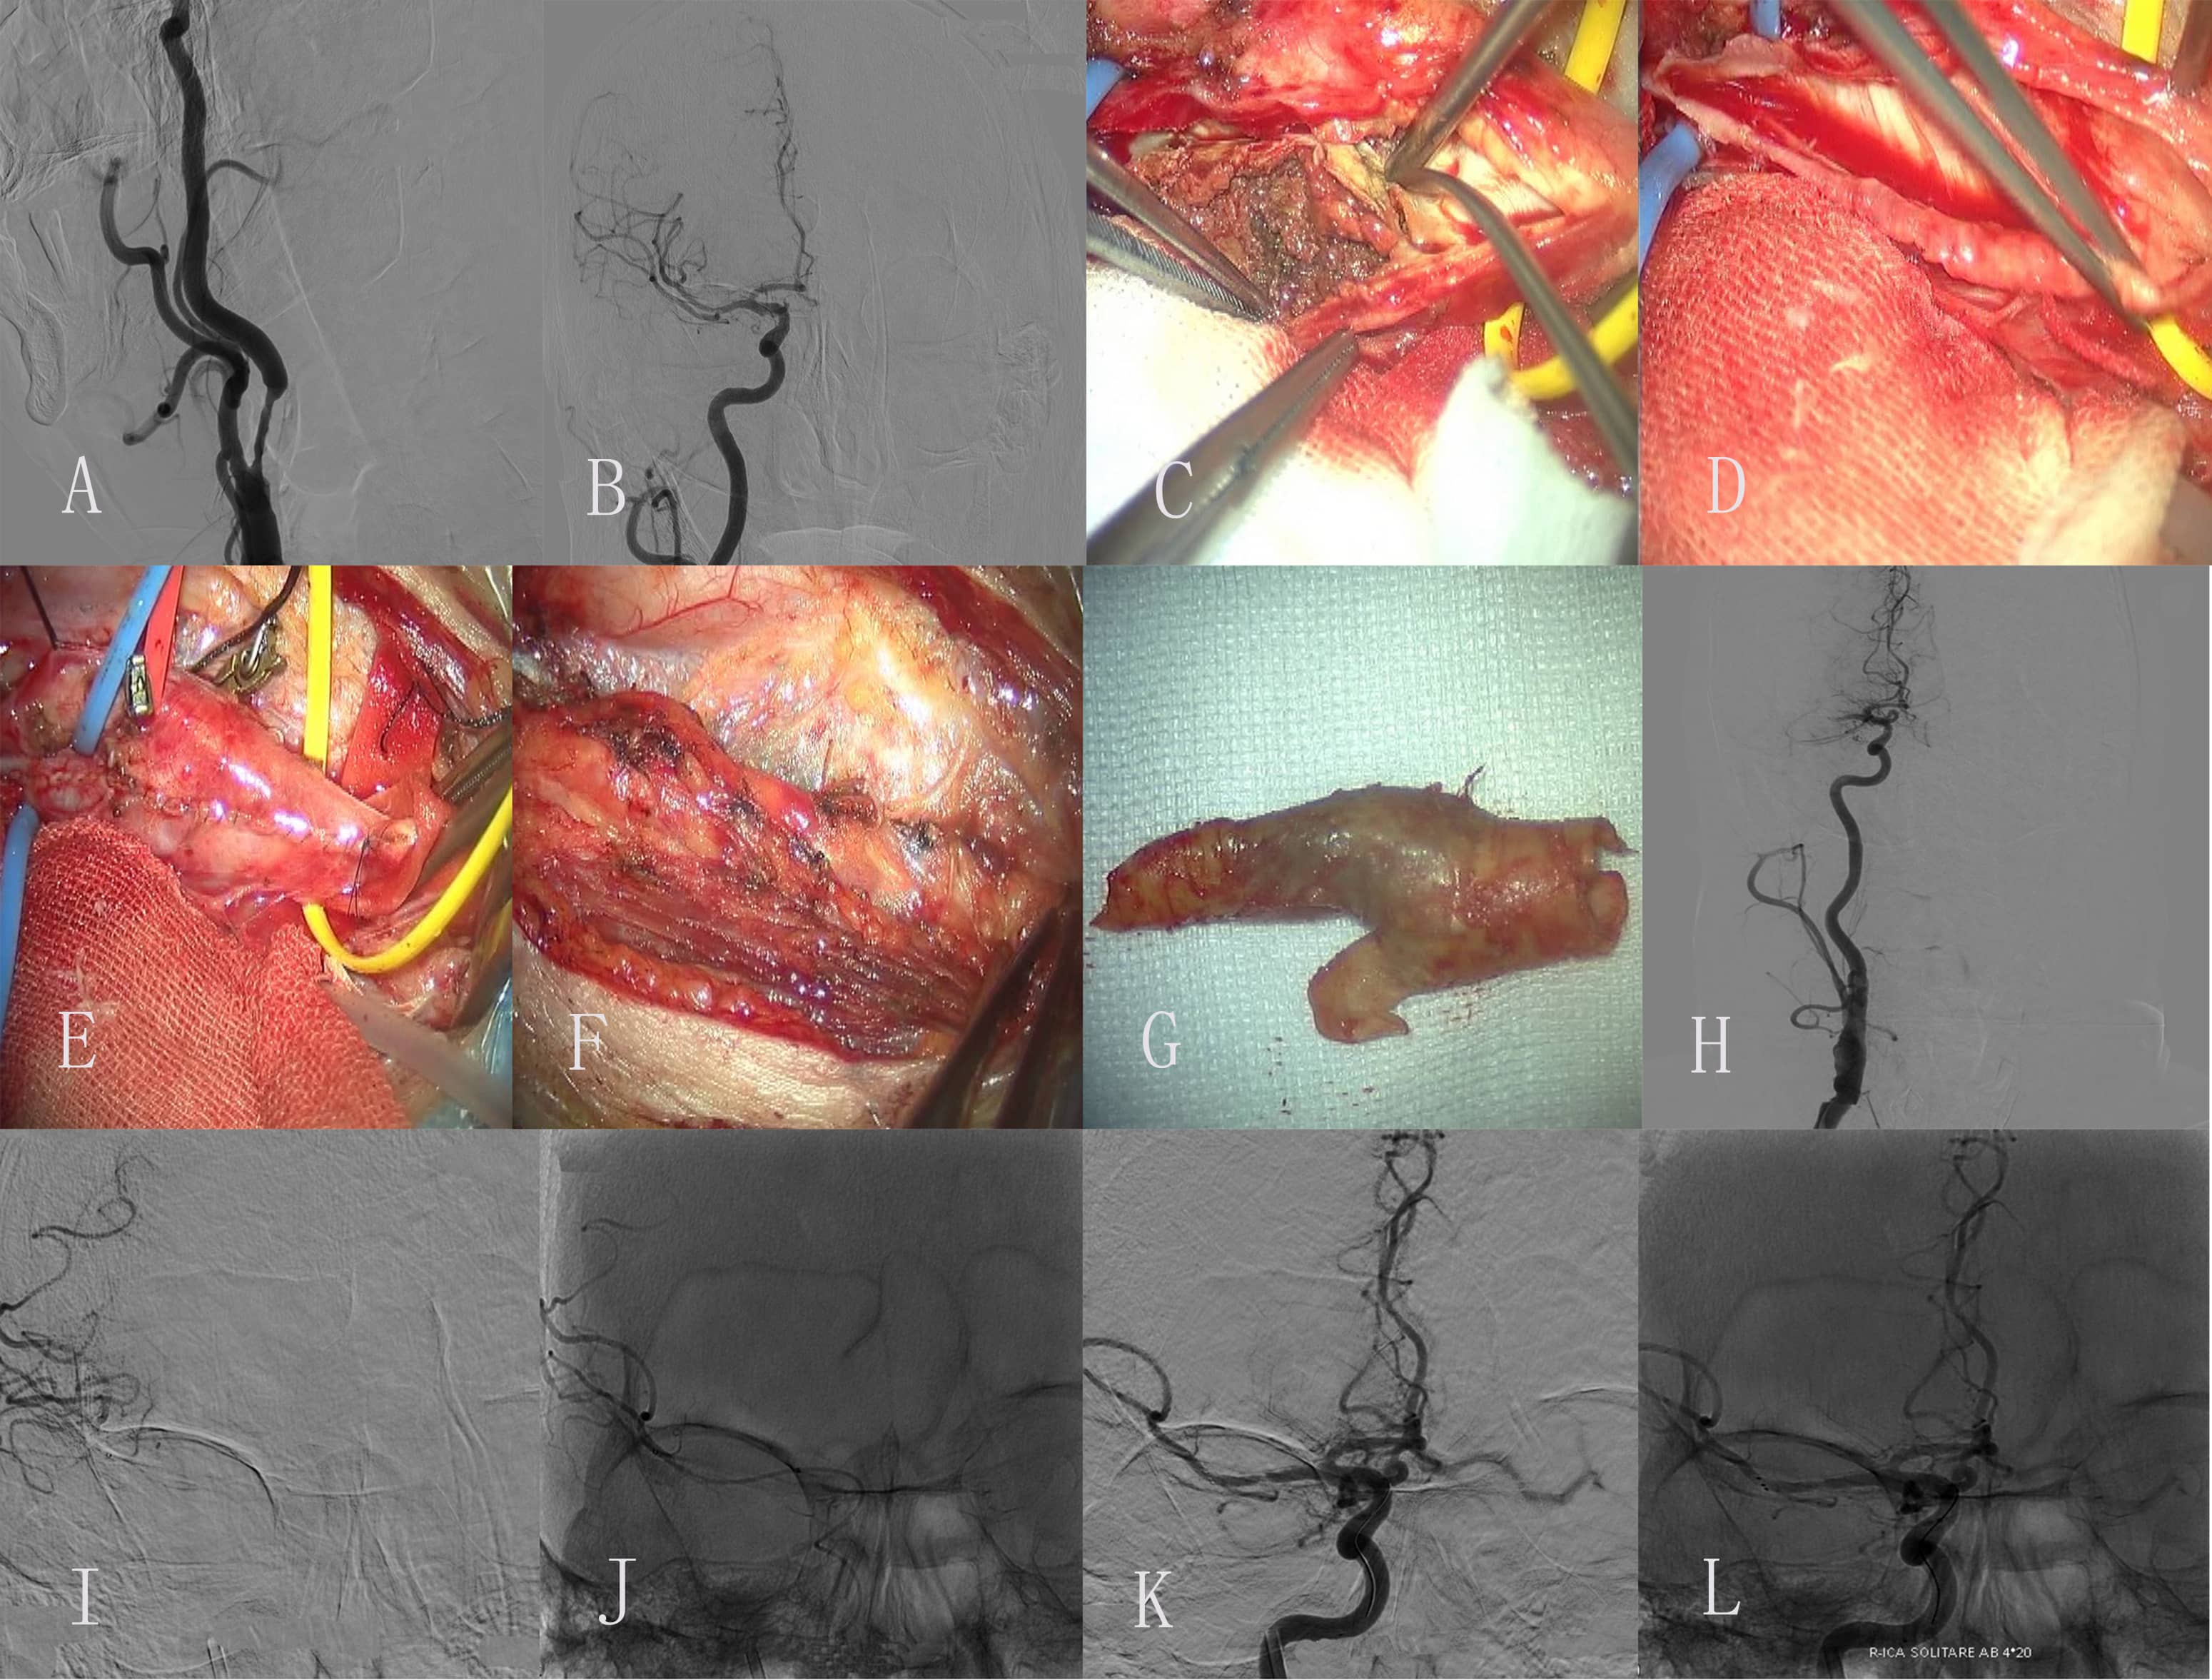

Fig. 2.Images of Case 2. (A,B) Preoperative left middle cerebral artery (MCA) and anterior cerebral artery (ACA) arteriogram revealed normal. (C,D) Preoperative left common carotid artery (CAA) arteriogram revealed a severe proximal internal carotid artery (ICA) stenosis. (E) Exposure of diseased vessel. (F) The endometrium of the CCA was dissected longitudinally and presented plaque. (G) Completed removal of plaque. (H) Incision suture. (I) Embolus was formed in carotid endarterectomy (CEA). (J) The thrombotic plaque disappeared after 0.5 mg tirofiban was administered to the artery. (K,L) Postoperative left ICA arteriogram revealed normal.